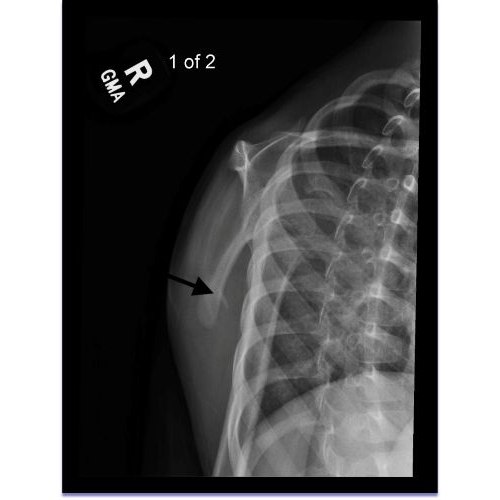

| Monkey Bar Mishap: A Unique Scapulothoracic Injury And Presentation - Page #3 | |||